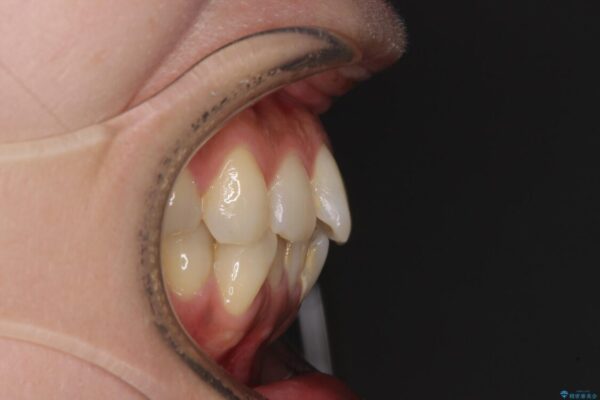

治療途中

• インビザラインによる矯正治療と奥歯のインプラント治療 治療途中画像